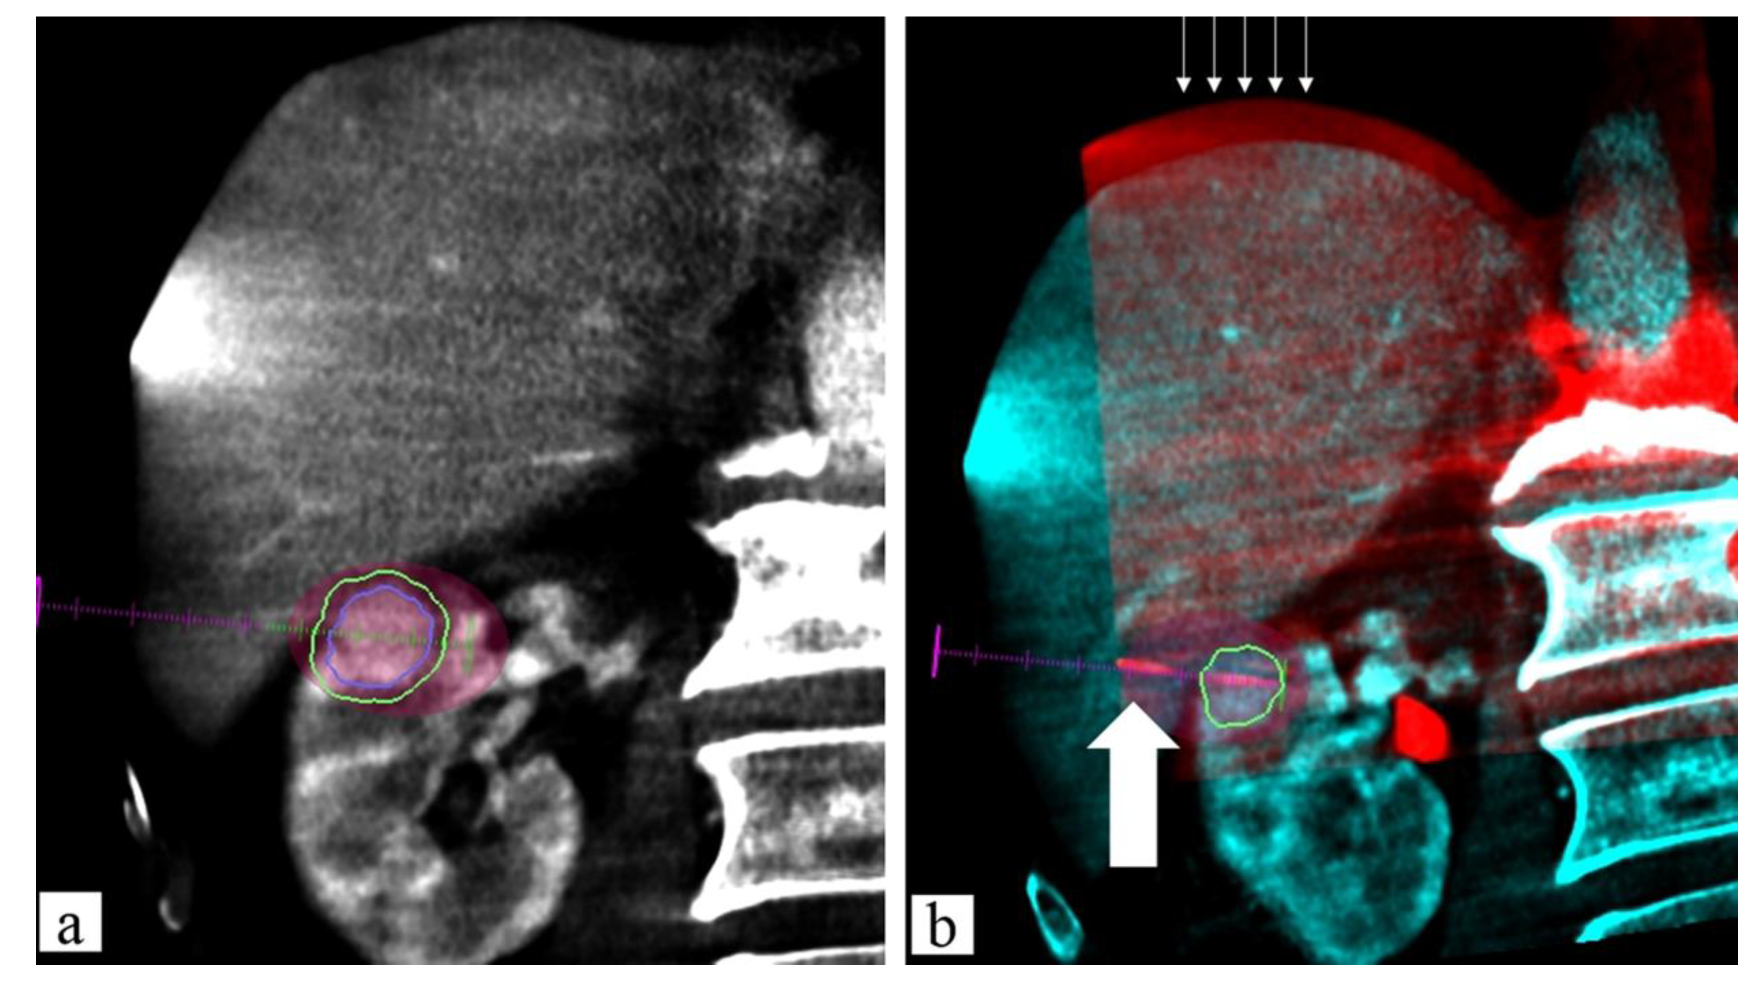

- Carriero, S.; Della Pepa, G.; Monfardini, L.; Vitale, R.; Rossi, D.; Masperi, A.; Mauri, G. Role of Fusion Imaging in Image-Guided Thermal Ablations. Diagnostics 2021, 11, 549. [Google Scholar] [CrossRef] [PubMed]

- Floridi, C.; Radaelli, A.; Pesapane, F.; Fumarola, E.M.; Lecchi, M.; Agostini, A.; Giovagnoni, A.; Carrafiello, G.; Wood, B. Clinical Impact of Cone Beam Computed Tomography on Iterative Treatment Planning during Ultrasound-Guided Percutaneous Ablation of Liver Malignancies. Med. Oncol. 2017, 34, 113. [Google Scholar] [CrossRef] [PubMed]

- Monfardini, L.; Orsi, F.; Caserta, R.; Sallemi, C.; Della Vigna, P.; Bonomo, G.; Varano, G.; Solbiati, L.; Mauri, G. Ultrasound and Cone Beam CT Fusion for Liver Ablation: Technical Note. Int. J. Hyperth. 2018, 35, 500–504. [Google Scholar] [CrossRef] [Green Version]